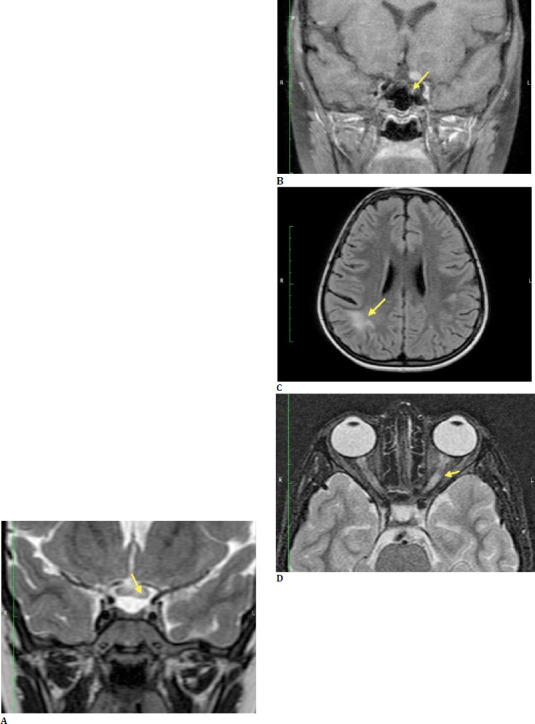

Case series: In the first case, a 36-year-old man came in with a left-sided headache and isolated third nerve palsy. Detailed investigations led to the discovery of a supraclinoid internal carotid artery aneurysm, necessitating prompt neurosurgical intervention. The second case featured a 74-year-old man with complete drooping of his right eyelid. The diagnosis of complete third nerve palsy led to further tests, which uncovered multiple myeloma. The third case involved a 19-year-old girl who had persistent double vision and bilateral ptosis. A collaborative effort between ophthalmologists and neurologists revealed Miller Fisher syndrome, which was successfully treated with intravenous immunoglobulins. Lastly, the fourth case described an 8-year-old girl who presented with optic neuritis. A thorough ophthalmological evaluation led to the diagnosis of Neuromyelitis Optica Spectrum Disorder, enabling early treatment and significant improvement.